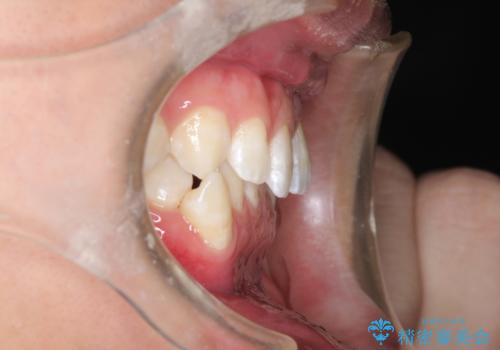

- 前歯がガタガタ、下の犬歯が飛び出ているのを主訴に来院されました。

下の奥歯を後方へ移動させてスペースを確保して、前歯を並べる計画としました。